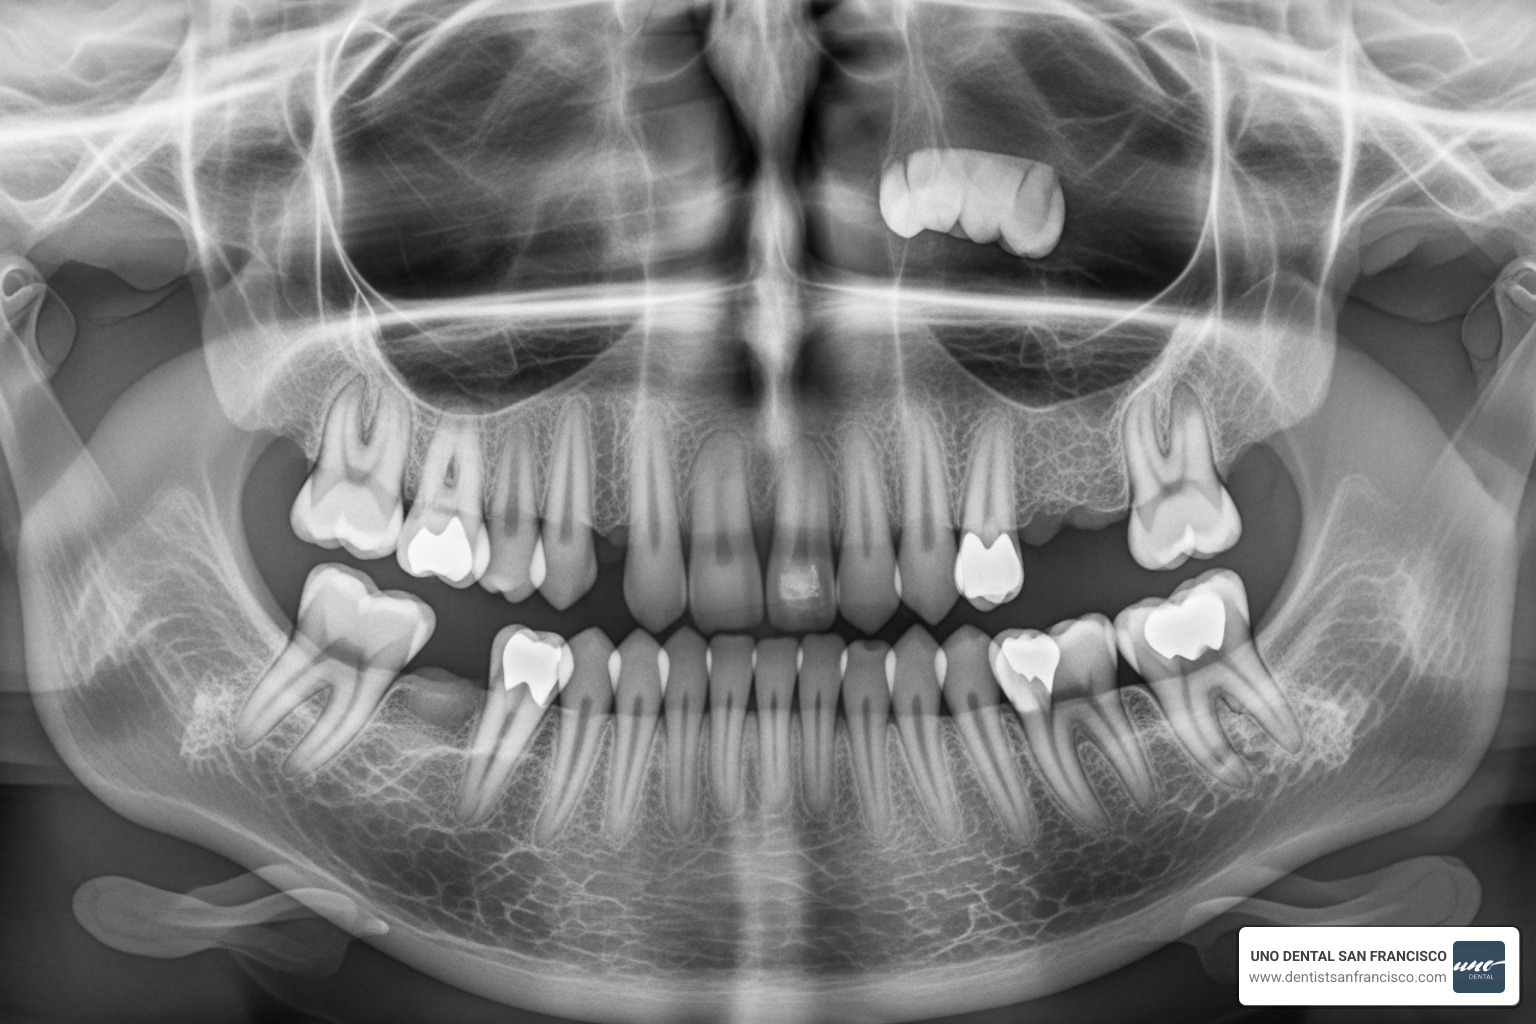

- Diagnostic Imaging: Panoramic X-rays ($60 - $150) or 3D CT scans for complex cases ($200 - $400) are needed to see the tooth's position.

- Proximity to Nerves: If a tooth is near the inferior alveolar nerve, your surgeon must use extreme precision to avoid damage, which may require specialized 3D imaging and advanced techniques. The American Association of Oral and Maxillofacial Surgeons offers an overview of these complexities.